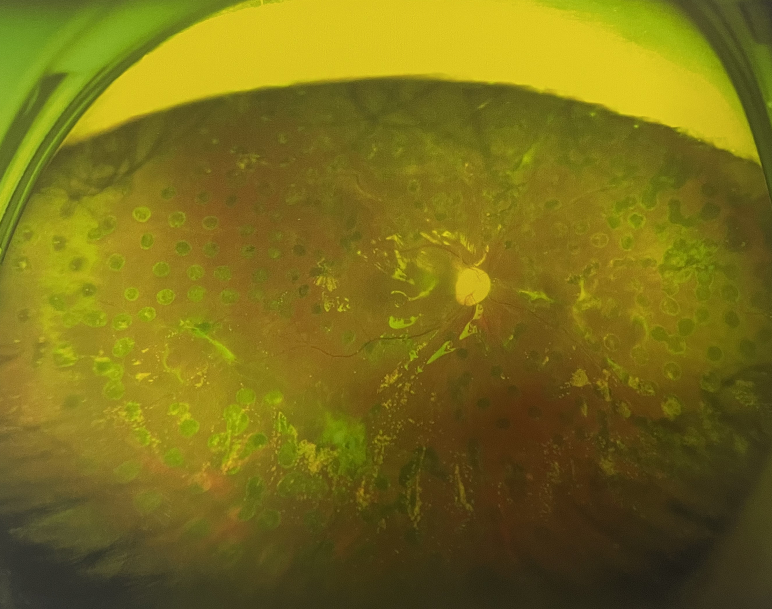

右眼術(shù)后

張小虎醫(yī)生為王女士進(jìn)行右眼玻璃體腔注藥術(shù),3天后進(jìn)行右眼23G玻璃體切割術(shù)后視力有所提升。

4個月后王女士來院取硅油,取油后視力恢復(fù)到0.6。“當(dāng)時來的時候真的只能看到模糊的影子,特別害怕覺得完了,想說眼睛估計要瞎了,沒想到手術(shù)后視力竟然提升了,現(xiàn)在也看得比較清楚了。”王女士說到。

張小虎醫(yī)生表示,糖網(wǎng)病進(jìn)展到嚴(yán)重增殖期帶來的視力損傷往往是極其嚴(yán)重的,目前王女士右眼從術(shù)前0.02恢復(fù)到術(shù)后0.6,已屬十分難得。